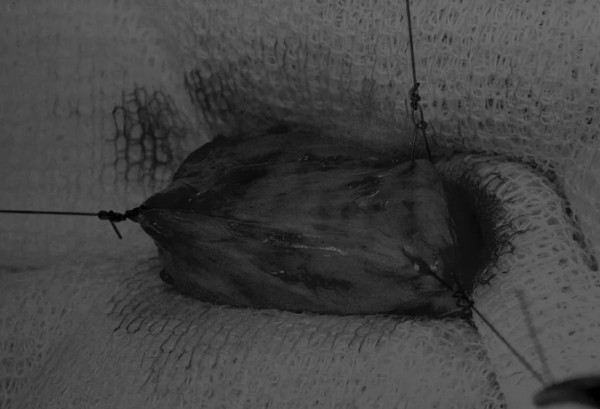

完成膀胱内冲洗后,应通过导尿管反向冲洗膀胱;砂样结石和血块会被冲到切口表面(图5)

图5 通过导尿管注入无菌生理盐水反向冲洗,可以去除微小的结石(箭头)和夹杂在膀胱黏膜皱褶中的砂样结石,以及可能在手术中形成的血块